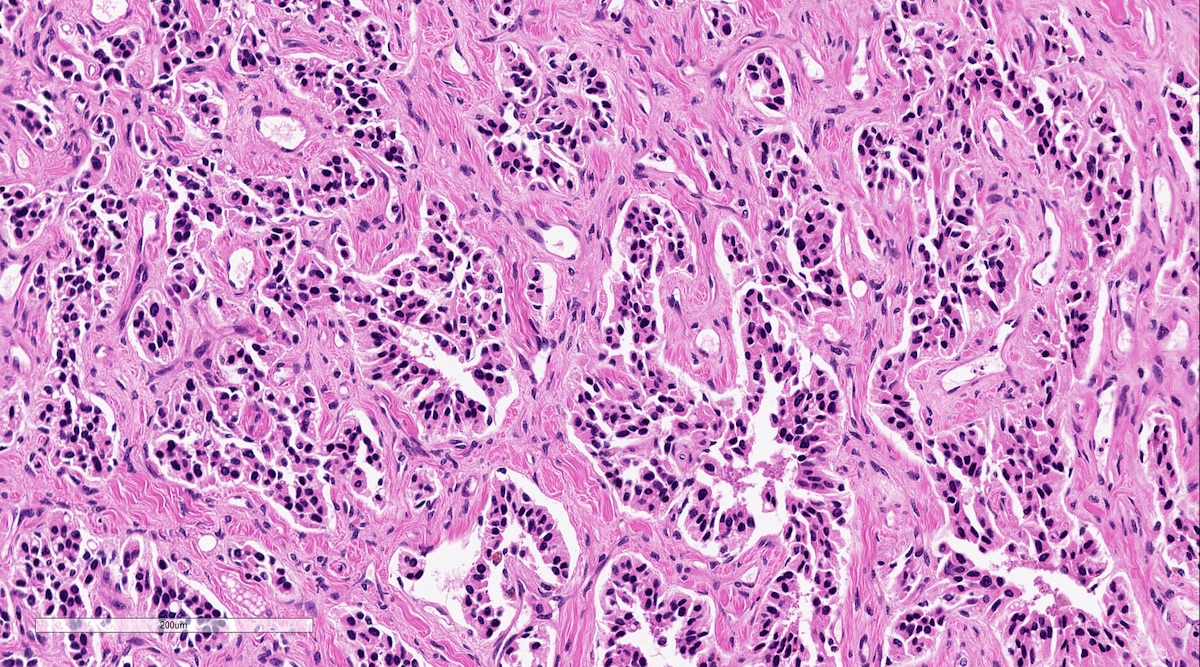

Microscopic (histologic) description

- Prevailing histologic pattern: epithelioid chief cells arranged in distinctive clusters / nests (zellballen pattern), separated by prominent fibrovascular stroma (J Clin Med 2018;7:280)

- Trabecular pattern: ribbons or cords of epithelioid cells divided by fibrous bands

- Other patterns: pseudorosette, angioma-like, spindled and sclerosing

- Chief cells: round, oval to polygonal cells with abundant granular basophilic, eosinophilic or amphophilic cytoplasm (Surg Pathol Clin 2019;12:951)

- Intracytoplasmic hyaline globules may be present in sympathoadrenal paragangliomas

- Giant multinucleated cells and bizarre cells can be present (Srp Arh Celok Lek 2002;130:7)

- Rarely, elongated and spindle shaped cells with a sarcomatoid appearance may be found

- Scattered ganglion cells can be seen

- May have nuclear atypia

- May have dysmorphic vessels, melanin-like pigment (neuromelanin) (pigmented paraganglioma), amyloid, abundant stroma and osseous metaplasia (Diagn Pathol 2012;7:77, Hum Pathol 1992;23:33)

- No or rare mitotic figures except in highly aggressive rapidly proliferating lesions

- May have focal chronic inflammatory infiltrate

- Necrosis is unusual except in patients who have undergone preoperative tumor embolization

- Special histopathologic features usually related to genetic syndromes:

- VHL syndrome: prominent stromal edema, clear cytoplasm and lipid degeneration (Am J Surg Pathol 1987;11:480)

- SDHx related syndrome: granular eosinophilic cytoplasm (Am J Surg Pathol 2020;44:422)

- MEN2 syndrome: unilateral or bilateral adrenal medullary hyperplasia (Neoplasia 2014;16:868)

Microscopic (histologic) images

Contributed by Luvy Delfin, M.D. and Sylvia L. Asa, M.D., Ph.D.